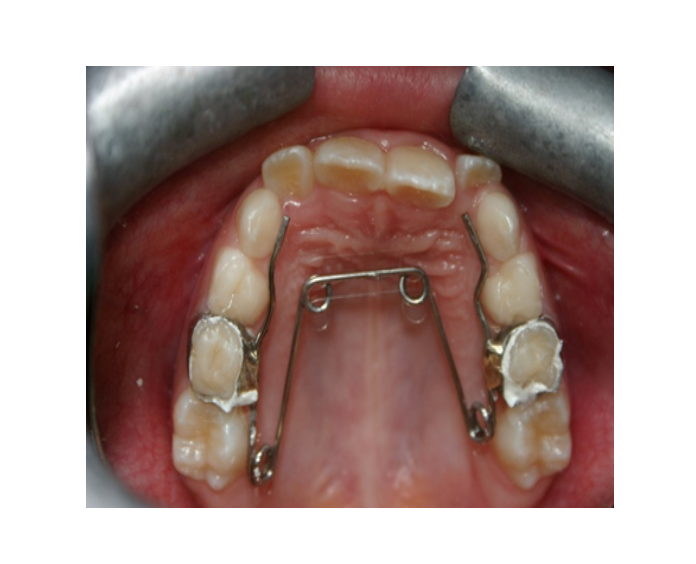

Mordida Cruzada posterior unilateral